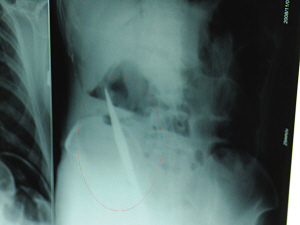

X光片上,尖刀清晰可見。

從男子體內(nèi)取出的尖刀足足有19厘米長。

銅山一58歲男子因服毒被送到醫(yī)院搶救,可醫(yī)生采取搶救措施后卻發(fā)現(xiàn)效果不佳。后來經(jīng)細致檢查,醫(yī)生有了個驚人的發(fā)現(xiàn),該男子的體內(nèi)竟然有一把尖刀,醫(yī)生通過手術(shù)將位于其腹部右側(cè)橫結(jié)腸下緣的尖刀取了出來。這把尖刀足足有19厘米長!據(jù)醫(yī)生推測,這把刀應(yīng)該是從肛門推進體內(nèi)的,不知男子為何想以如此殘酷的方式結(jié)束自己生命。由于搶救及時,該男子已暫時脫離危險。

6日上午,記者在徐州礦務(wù)集團總醫(yī)院重癥監(jiān)護室見到了這名男子,目前他雖然已經(jīng)恢復(fù)了意識,但還不能開口說話,需要呼吸機輔助呼吸。據(jù)醫(yī)生介紹,4日中午12時左右,這名男子因服毒輕生被緊急送到醫(yī)院進行搶救,之前,這名男子已經(jīng)在當(dāng)?shù)剜l(xiāng)鎮(zhèn)醫(yī)院進行了近20小時的治療,但效果不佳。“病人被轉(zhuǎn)院到礦總院時已神志不清,血壓極低,處于休克狀態(tài)。”救護人員給男子洗胃、初步處理以后,發(fā)現(xiàn)男子呼吸急促,于是趕緊給他拍片檢查。結(jié)果讓所有的醫(yī)生大吃一驚,竟有一把尖狀異物橫在該男子腹腔內(nèi)!當(dāng)天下午5時30分,輕生男子被推上了手術(shù)臺。經(jīng)過40多分鐘的手術(shù),該男子腹腔被打開,手術(shù)醫(yī)生發(fā)現(xiàn),男子體內(nèi)的金屬狀異物竟然是一把長19厘米的尖刀!